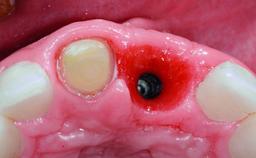

Replacement of an Upper Right Central Incisor with Root Resorption: Ridge Preservation, Early Placement of an RC Bone Level Implant

A 49-year-old female patient was referred for implant therapy to replace the upper right central incisor (tooth 11). The tooth had been assessed by an endodontist who diagnosed a vertical fracture of the root. The tooth had a hopeless prognosis and needed to be extracted. The patient was healthy and was not taking any medications. She was allergic to penicillin. The patient had high esthetic demands but her expectations were realistic. The extraoral examination revealed no facial asymmetries. The right temporomandibular joint demonstrated an opening click but was otherwise asymptomatic. The lip line was high with a significant gingival display.